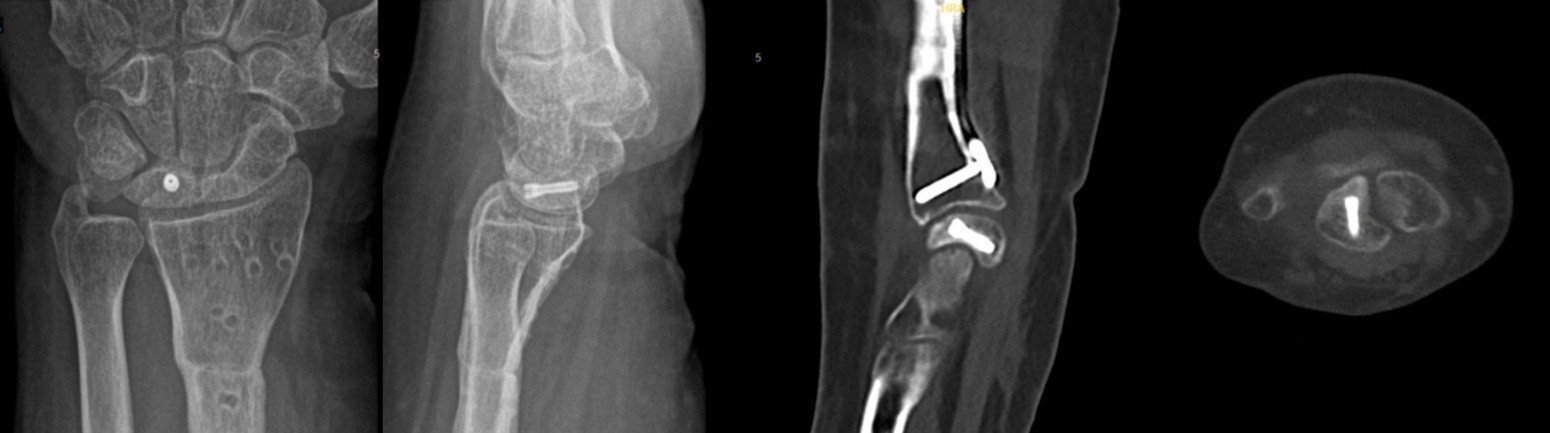

Here, we present two cases of Kienböck’s disease classified as Lichtman stage IIIc, characterized by complete osteonecrosis and a coronal fracture of the lunate, without associated cartilage damage. Both patients underwent a medial closing wedge osteotomy of the radius combined with compression screw fixation of the lunate fracture. The two patients were female, aged 42 and 47 years, with a history of wrist pain. Pre-operative imaging included standard wrist radiography, which revealed a negative ulnar variance (radiographic ulnar index), computed tomography (CT) confirming the presence of a lunate fracture, and MRI demonstrating osteonecrosis (showing a hypointense signal on T1-weighted sequences and a hyperintense signal on T2-weighted sequences, with no gadolinium enhancement). No signs of carpal instability or cartilage degeneration were observed in the surrounding structures.

- Patient A: A 42-year-old right-handed housewife presented with significant pain and stiffness in her dominant wrist persisting for 4 months. She had no history of trauma and was a non-smoker. Her medical history was notable for diabetes and a prior episode of deep vein thrombosis in the lower limb several years earlier (Fig. 1, 2, 3).

Figure 1: X-ray radiographic ulnar index of −3 mm.

Figure 2: Computed tomography scan.

Figure 3: Magnetic resonance imaging.